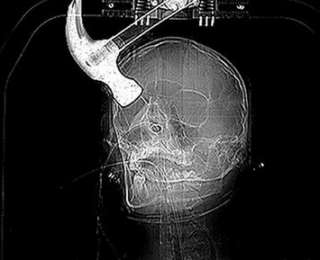

Рентгеновский снимок: